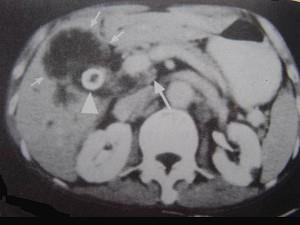

问题 男,68岁,上腹部隐痛二月余,CT检查如图,最可能的诊断是 ( )

选项 A、胆囊息肉 B、胆囊区转移瘤 C、胆囊癌(肿块型) D、胆囊腺肌增生症 E、慢性胆囊炎

答案 C